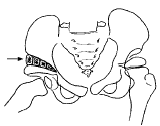

自髂嵴中点以下开始,向前延伸至髂前上棘以下,继续至腹股沟中点下行约3~4cm,做Salter切口,逐层暴露关节囊。复位后,在关节囊外做不完全的髂骨截骨,自髂前上棘开始在髂翼处取一长约4~5cm,底边3~4cm大小的三角形骨块,再将其切成3~4块大小不等的三角形。将截骨远端向前下外方向旋转后,在两断端垂直并列嵌入3~4块三角形骨块,注意尽可能填塞所有的断端间隙。大的植骨块嵌入断端外侧,小的植骨块置于内侧间隙,即可使植骨块嵌牢而勿需任何内固定(图1)。检查髋关节中心复位后,缝合关节囊及各层组织。术后用单髋“人”字石膏固定或双下肢外展位石膏固定2~4周。术后3d内常规摄骨盆X线正位片。卧床期间进行除过度内收外的髋关节各方向训练和肌力训练,3个月后可下地负重行走。

(箭头处为截骨断端垂直嵌入的植骨块)

图1 植骨示意图